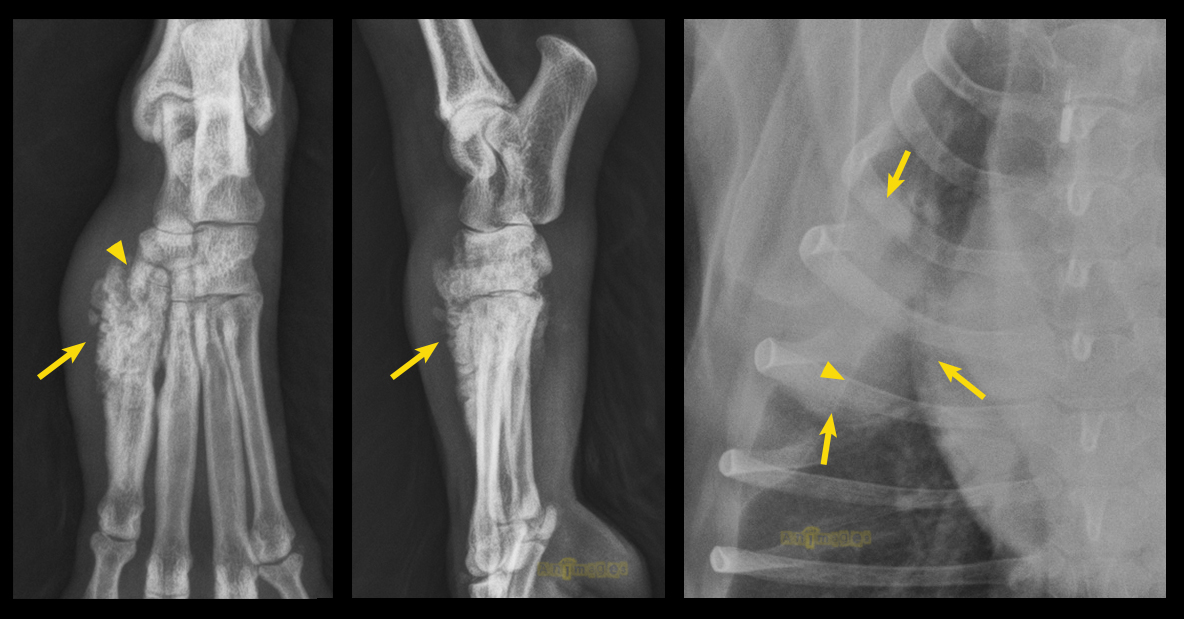

Plusieurs choses nous agaçaient dans la présentation clinique et radiographique de ce cas atypique… D’abord, la lésion osseuse semblait bien monostotique (un seul os atteint) sur la dorsoplantaire (DP), même si la latérale donnait l’impression que la rangée distale du tarse était affectée. Sur la DP, on remarque que la tête du métatarsien II est élargie et déborde proximalement et dorsalement pour se superposer aux os de la rangée distale du tarse qui paraissent intacts. La tête de cet os est remplie de foyers lytiques (tête de flèche) alors qu’une réaction périostique irrégulière – en partie bien définie (proximalement, flèches) et en partie mal définie (distalement) – s’étend distalement (faces médiale, dorsale et plantaire). Les tissus mous adjacents sont épaissis.

La possibilité d’ostéopathie hypertrophique fut considérée, mais celle-ci ne provoque généralement pas de lyse osseuse et implique typiquement les membres de façons symétriques et les faces axiales et abaxiales des os appendiculaires (bien que ce ne soit pas toujours le cas). En voici deux beaux exemples (chiens avec masse pulmonaire – à gauche – et masse oesophagienne – à droite).

Pour ce qui est des poumons, une seule grosse lésion fut identifiée (flèches sur la figure 1) , alors que les métastases d’ostéosarcome sont le plus souvent multiples et plus petites que celle-ci. Notez la fine scissure (tête de flèche) entre les lobes cranial et moyen du poumon droit.